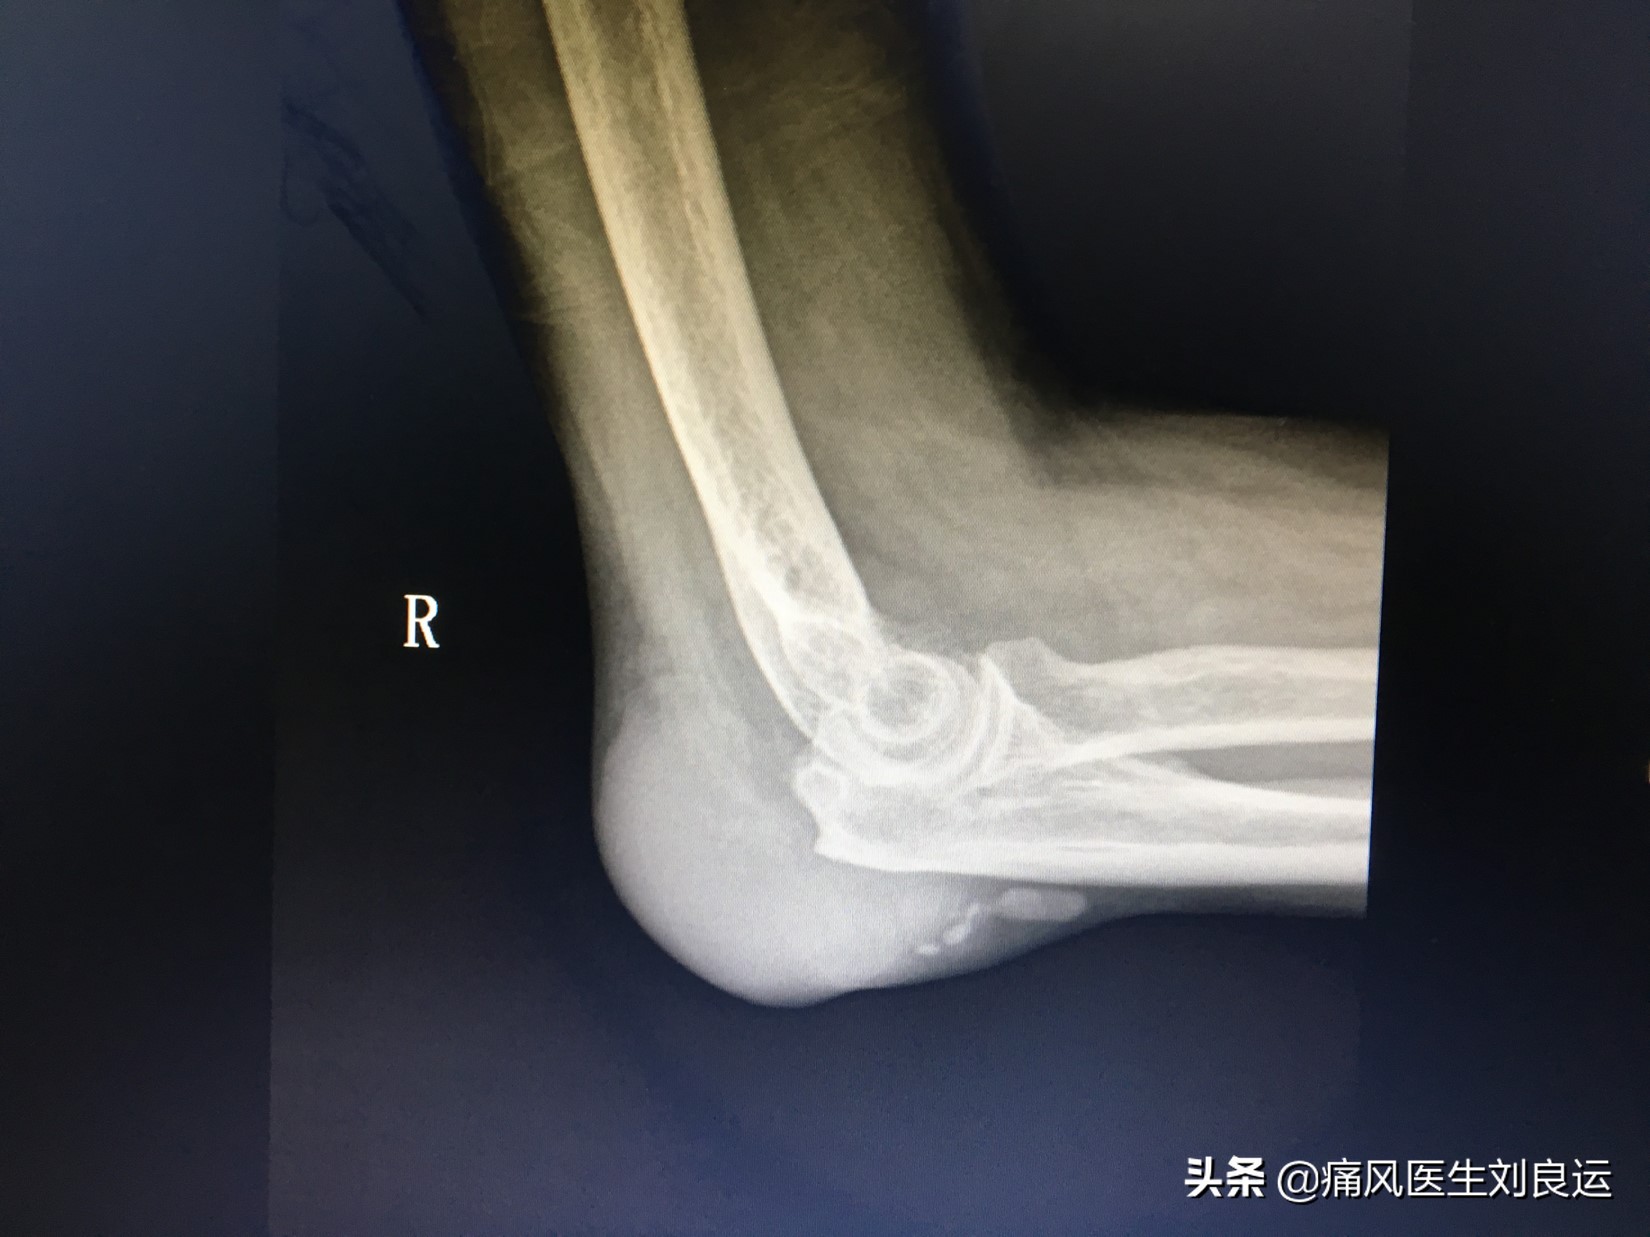

X线下肘关节痛风石

痛风石可见于任何关节软骨(透明软骨或纤维软骨)、滑膜、触鞘及其周围软组织;好发于外耳的耳轮、尺骨鹰嘴、指间和掌指关节、指端皮肤、手掌、腕关节、跖趾、踝关节、足背、足底、膝关节等处;少数病人可出现在鼻软骨、舌、声带、眼睑、主动脉、心瓣膜和心肌;大动脉、心肌、主动脉瓣、二尖瓣、三尖瓣、舌、会厌、也会出现痛风石;躯干部,如肩、胸、腹、背、腰、臀等处少见,大腿及上臂等处少见;可在关节附近的滑囊膜、腱鞘与软骨内发现。内压增高,常常会使局部皮肤膨胀、紧张、菲薄、发亮。加上尿酸盐结晶的侵蚀作用,覆盖其上的皮肤完整性受到破坏,抗牵拉性下降,一旦因摩擦、受压、受冻以及创伤等原因可发生溃烂,“牙膏样”白色尿酸盐结晶物质就会从破溃的洞里“漏出来。